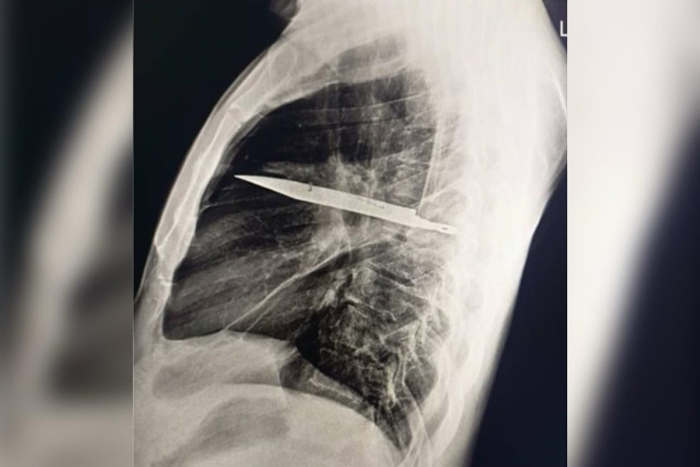

Foto: Journal of Surgical Case Reports

Raio-X revelou lâmina no tórax

Durante a investigação, os médicos realizaram exames de imagem e encontraram a lâmina presa no lado direito do tórax, próxima à escápula. Apesar do tamanho, o objeto não atingiu órgãos vitais.